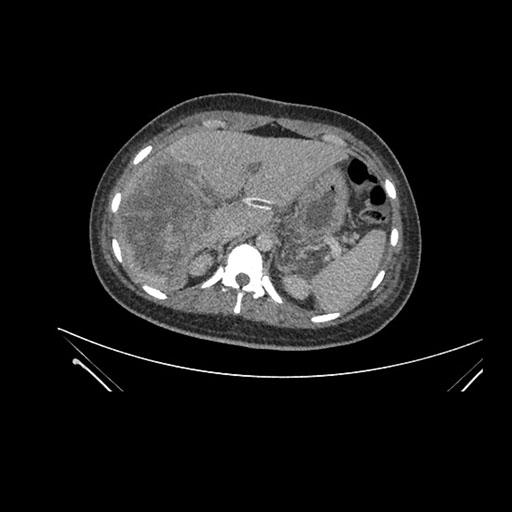

Imaging Analysis

Look through the patient's CT scan to identify any areas of concern for the necessary procedure.

Axial Venous